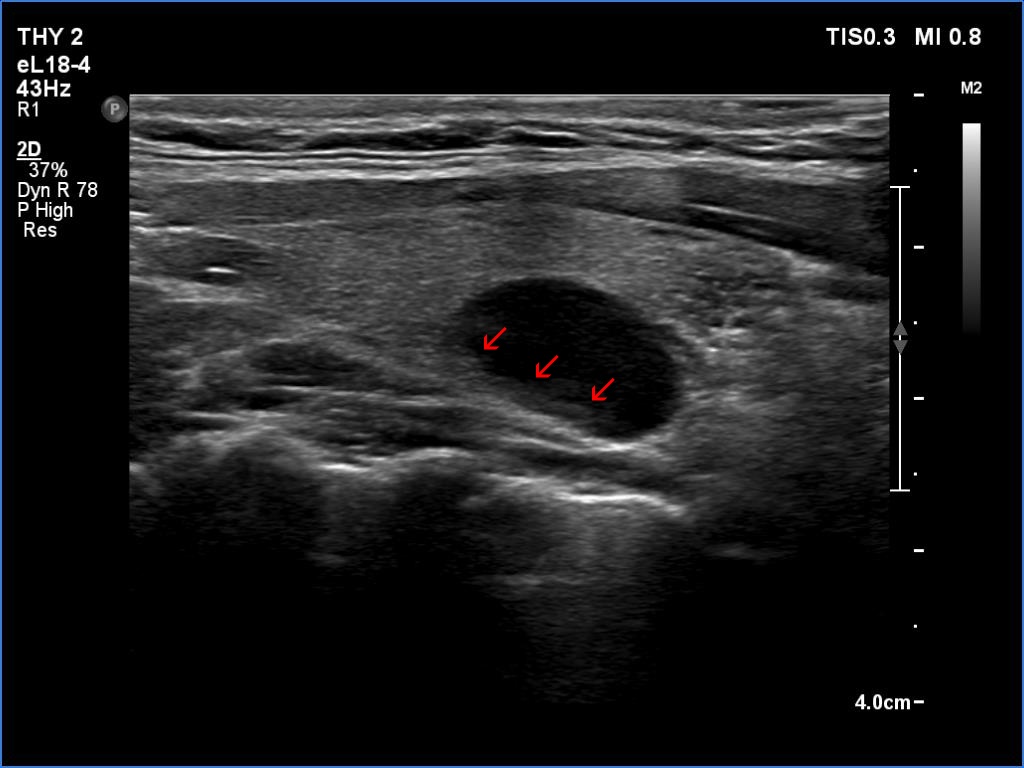

Longitudinal scan |

This is an almost completely cystic lesion, however it does not meet the criteria of a pure cyst. The wall thickening (yellow arrows) is ambiguous but there is a tiny solid-appearing area in the dorsal wall (red arrows). In systems which do not use the term 'almost completely cystic lesion', this nodule should be categorized as a peripheral-type cyst.